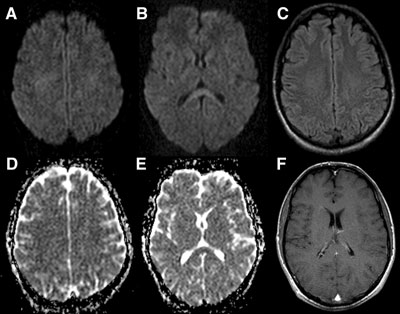

•急性期表现为胼胝体弥漫性肿胀,T1WI呈稍低信号,T2WI及FLAIR呈稍高信号,以矢状位观察最佳,可单独累及胼胝体压部或整个胼胝体,DWI呈高信号,ADC图呈低信号,部分患者可观察到脑室周围白质或内囊受累,少见皮层受累,表现为扩散受限,不强化和强化病例均可见到。如果增强扫描可见胼胝体有不同程度强化,呈小灶状或不规则斑片状,系血脑屏障破坏所致(如本例),本例患者处于急性期。

原发性胼胝体变性急性期:T2WI矢状位(A)清晰观察到弥漫胼胝体病变,FLAIR呈高信号(B),DWI呈高信号(C),ADC图呈低信号。